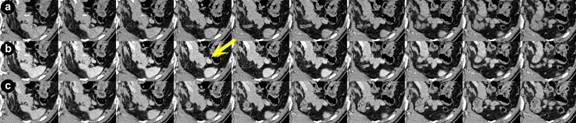

A sixty-seven-year-old man was referred for further examination and treatment of hypoglycemia. He underwent a left nephro-ureterectomy for renal pelvis carcinoma two years prior to admission. During routine follow-up, he was found to have symptomatic hypoglycemia with a serum glucose less than 50 mg/dL. Laboratory data showed no abnormalities except a serum glucose level of 52 mg/dL. IRI and CPR were not suppressed. Anti-insulin antibody was negative. Routine imaging studies including abdominal US, CT, MRI, and EUS failed to image a lesion. ASVS suggested an insulinoma in the body/tail of the pancreas. Early-phase thin-slice CT revealed a 10 mm nodular lesion, which was well enhanced and circumscribed in the tail of the pancreas on several slices in the 45-second series (Figure 3). IOUS revealed a low echoic tumor in the area suggested by images from the early-phase thin-slice CT scan, and enucleation of the 10 mm tumor was performed. The tumor was grade G1, with an MIB-1 index <1%. Immunohistochemistry showed chromogranin A (+), synaptophysin (+), insulin (+), glucagon (slightly +), somatostatin (-), and pancreatic polypeptide (-). His postoperative course was uneventful and is without recurrence 15 months after operation.

Figure 3. Axial CT scan of Patient #3 (slice thickness: 1 mm), at 25 seconds (a.), 45 seconds (b.), and 80 seconds (c.) after the administration of contrast agent, respectively. In the series at 45 seconds a 10 mm well-enhanced tumor is recognized more clearly than in other series, and this tumor is hard to discern in the series at 80-seconds. |